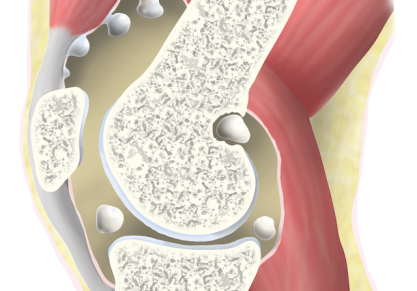

Причины синовиального хондроматоза коленного сустава, классификация, хирургическое лечение

Виды синовиального хондроматоза коленного сустава, причины появления. Методы диагностики, симптомы болезни. Хирургическое лечение, реабилитация, осложнения.